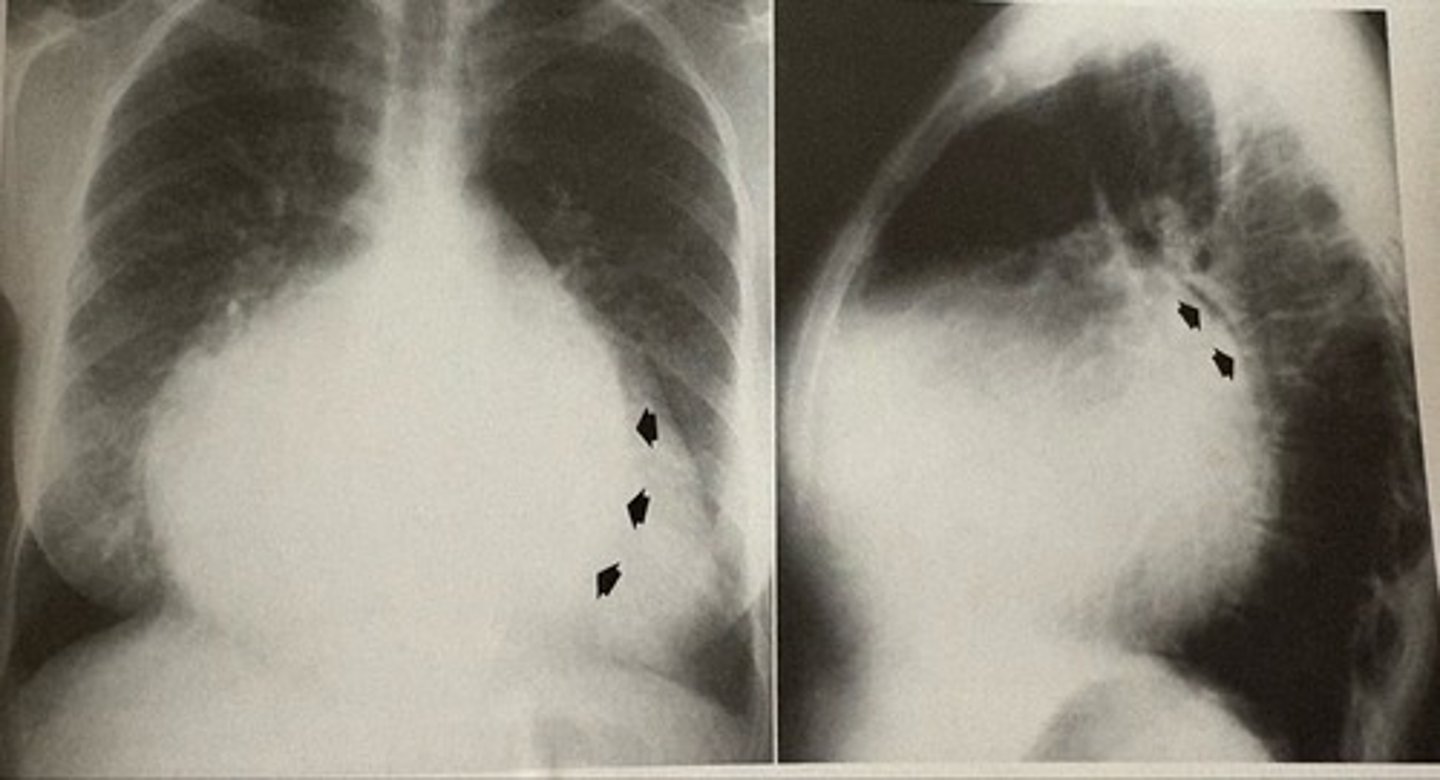

pericardial effusion

what pathology is present?